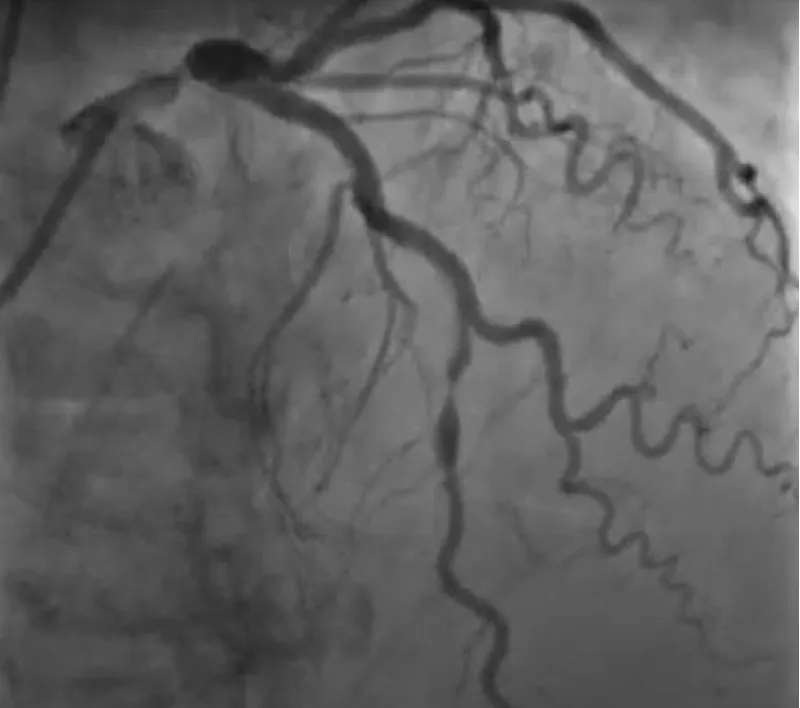

The clinical case concerns an 81-year-old woman with a history of systemic arterial hypertension, hypercholesterolemia, paroxysmal atrial fibrillation, chronic kidney disease, iron-deficiency anemia, and bilateral carotid atheromatosis for which she underwent a Carotid Endarterectomy (CEA) procedure. Additionally, she had a history of breast carcinoma, treated with surgery, subsequent chemotherapy, and ongoing Letrozole therapy. In 2019, the patient presented to the emergency department due to exertional dyspnea and low-threshold angina. During hospitalization, high average ventricular response (109 BPM) atrial fibrillation was diagnosed. Routine lab tests showed rising of hsTN-I (peak 800 pg/dL) and pro-BNP (peak 2476 pg/mL) and anemia Hb 9.1 g/dL. Echocardiography revealed severe depression of the left ventricular function (ejection fraction of 30%, with antero-apical akinesia) and low-flow-low-gradient aortic stenosis (mean gradient of 26 mmHg and AVAi of 0.5 cmq/m2 and SVi 29 mL/m2). So it was performed a Dobutamine stress Echo showed a rise of SVi up to 38 mL/m2 and a mean aortic gradient of up to 48 mmHg. Coronary angiography showed the right dominant coronary artery, of good caliber and course, with no angiographically significant lesions (Figure 1). The Left Main artery, with good caliber, had a 90% calcific stenosis at the distal segment, involving the proximal segment of the Left Anterior Descending artery. The Left Circumflex artery, with good caliber and course, presented a 30% ostial stenosis. The Intermediate Branch, with good caliber and course, showed 80% stenosis at the proximal segment (Figure 2). The Left Anterior Descending artery, also of good caliber and course, was diffusely atherosclerotic with a long, severely calcific 80% stenosis at the mid-distal segment (Figure 3). Therefore, the case was discussed by a multidisciplinary Heart team at our center. The STS score calculated indicated a mortality risk of 11.4%. Due to this high risk, surgical treatment was not considered, and the patient underwent a four-step percutaneous intervention. Before the intervention, a CT angiography was performed, revealing an aortic annulus area of 433.2 mm2, a perimeter of 75.3 mm, and a coronary height from the annulus of 10 mm. The right common femoral artery mean diameter was 6.1 mm2 and the external iliac artery was 8.4 mm2 with moderate tortuosity without significant calcification (Figure 4-6). Therefore, a 23 mm Edwards Sapien 3 valve was chosen. Our strategy consisted of 4 steps:

Figure 3: The Left Anterior Descending artery, also of good caliber and course, was diffusely atherosclerotic with a long, severely calcific 80% stenosis at the mid-distal segment.